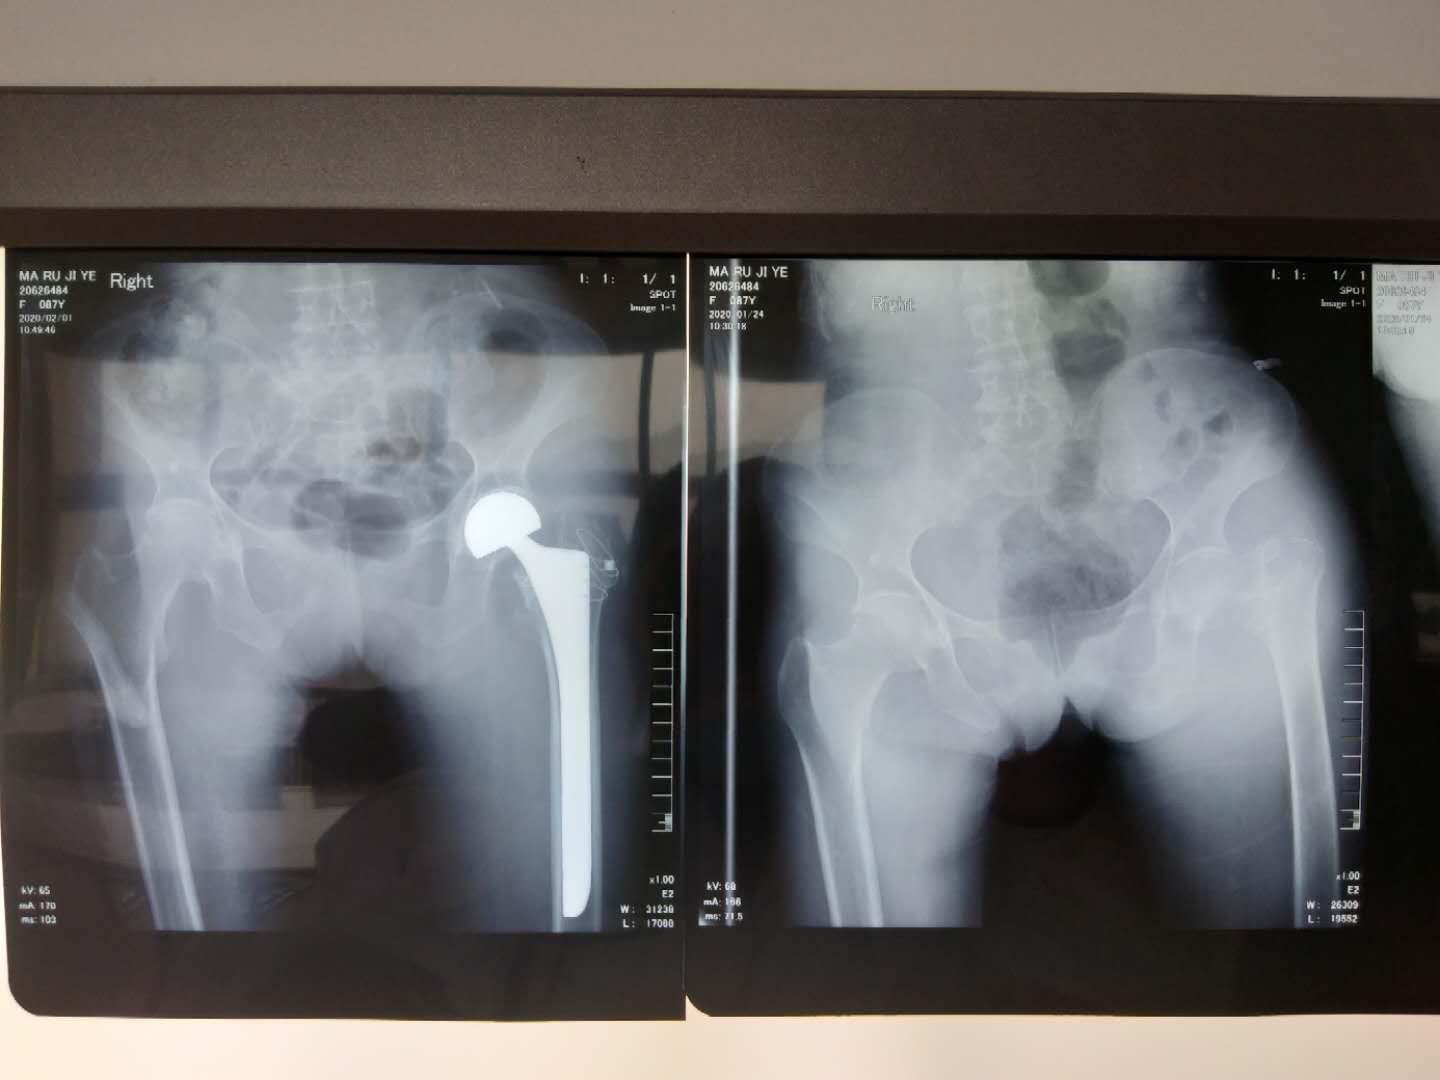

病例二:87岁,女,股骨颈基底部骨折。重度骨质疏松症,正细胞性贫血,给予人工股骨头置换术,大粗隆重建。术后鼓励患者尽早坐起,允许患肢在疼痛可耐受范围内完全负重,并由指导患者功能康复。术后3天下地行走。大大减轻护理压力。